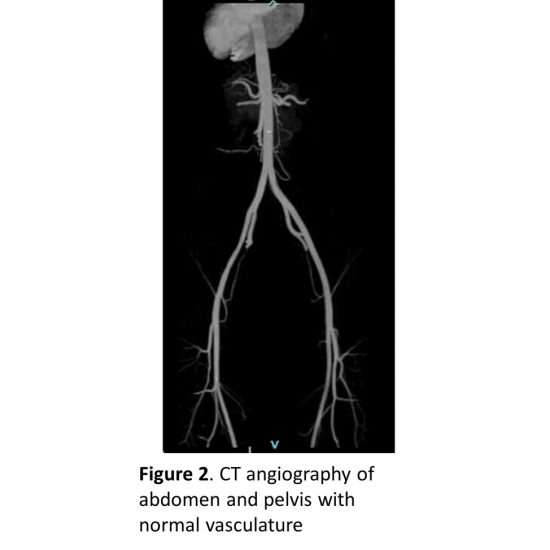

| A Rare Cause Of Unilateral Leg Pain In A Competitive Triathlete - Page #3 | |||